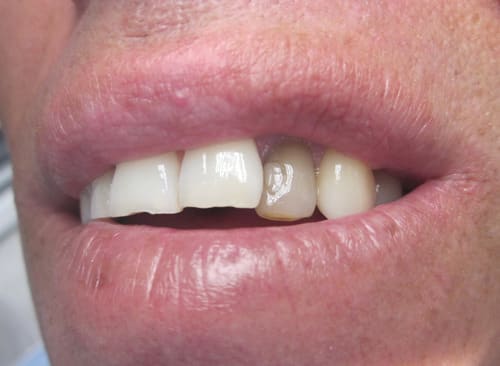

sur la photo "maquillage" on voit que le bord du provisoire a été un peu envahissant sur la canine, avec le bridge définitif la gencive est revenu a sa place, avec des bords foireux la gencive ne revient pas

Joli bridge.

Un peu surpris de voir que l'empreinte optique ne couvre pas toute l'arcade.